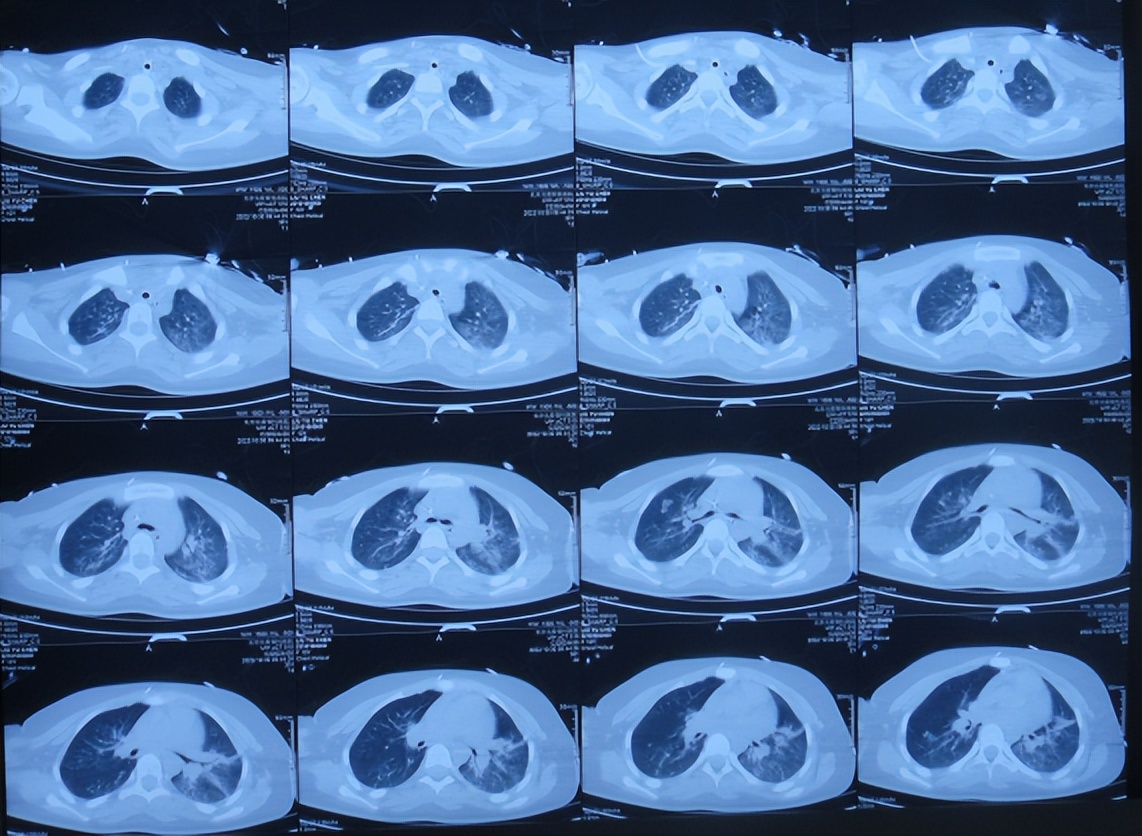

患儿于2022年10月10日,无诱因出现颈部疼痛,伴恶心呕吐、精神差,当时意识清楚,没有就诊,5天后即2022年10月16日,凌晨再次出现恶心呕吐多次,精神差,变得嗜睡,能被叫醒,就诊于山西省大同市浑源县某医院,查颅脑CT( 图-1 )示“小脑出血”,给予止血对症治疗。

图-1: 2022年10月16日颅脑CT上午11点

2022年10月16日(小脑出血当天晚上)住入李小勇脑脊液科。入院时:嗜睡,能被叫醒;时有恶心呕吐( 图-2 )。查头颅CT示小脑出血,脑室有扩张( 图-3 );肺部感染( 图-4 )。

图-4: 2022年10月16日肺部CT